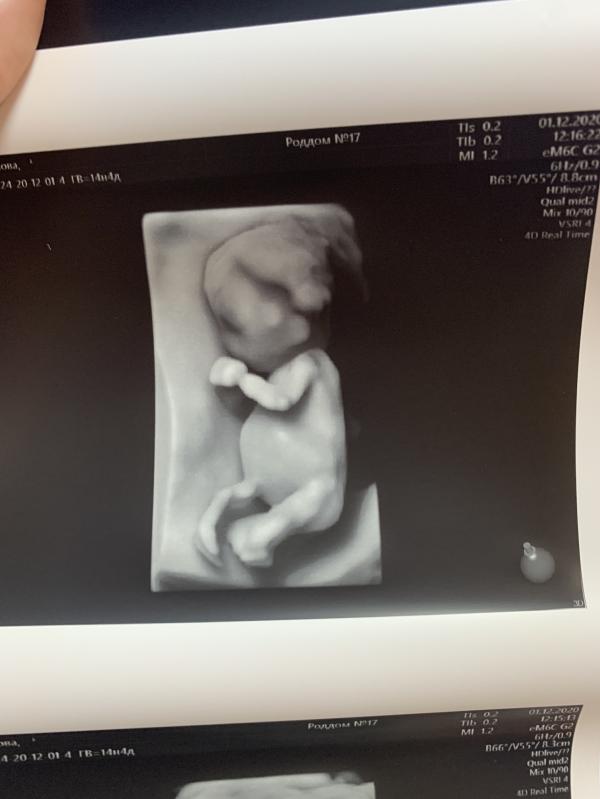

Итак, срок 14.4.

Пройдено очередное плановое УЗИ в 17 роддоме. На этот раз у Каштановой.

Дискордантность сохраняется 30%. Вес малышей 85 г и 122 г. Мочевой у второго большой, по фото видно разницу. Наблюдаемся дальше. Следующее УЗИ в МГЦ на Тобольской 10-11 декабря. Потом опять в 17 роддом 15 декабря. Очень часто видимся с малышами, но УЗИ я не боюсь, да и динамику надо наблюдать ☝🏻

Предположили пацанов 🙈 Так что будем полностью укомплектованной семьей 😂